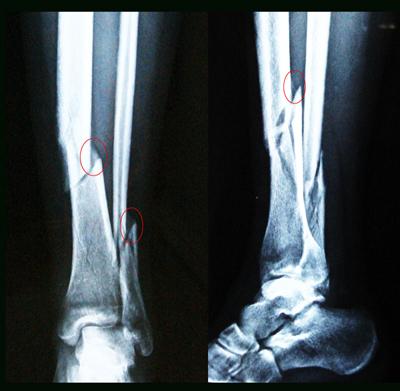

男59岁,胫骨骨裂,血管断裂,唯医,allinmd